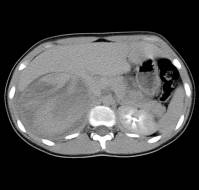

Fulminant pneumonia due to Mycoplasma pneumoniae (MP) is rare, despite the high prevalence of Mycoplasma infections in the general population. We report a case of at..

A report describes a case of a previously healthy 2-year-old girl who presented with six days of productive cough, high fever, and poor appetite. She was fully im..